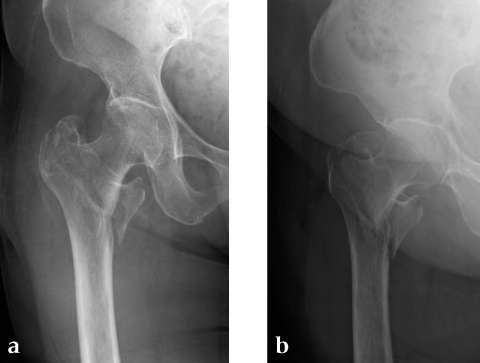

Case 3: 90-year-old male, injured by fall down.

Case provided by Toru Sato, Okayana, JP